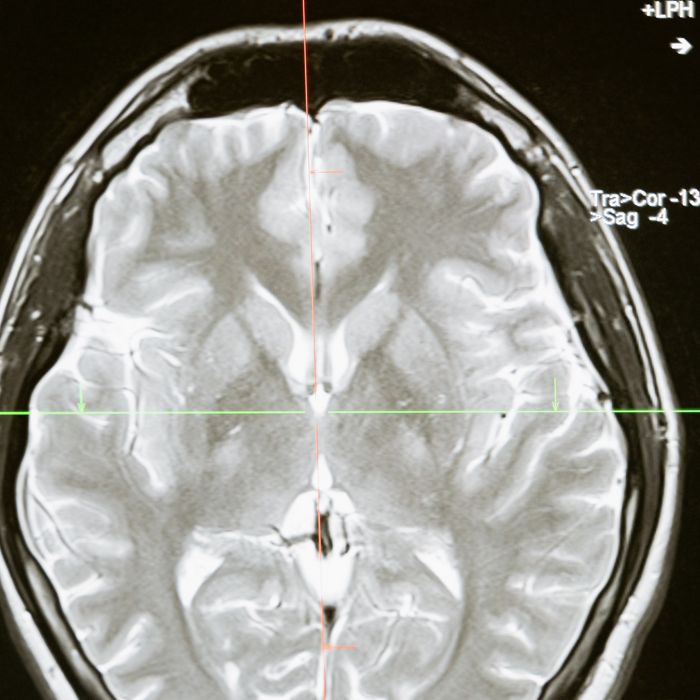

2050 - Mapeamento completo do Conectomo

Neste ano, conseguimos mapear o conectomo: uma representação matemática de todas nossas conexões neurais.

• Sabemos como o cérebro funciona

• Melhor interface cérebro-máquina

• Mais pertos de compreender consciência